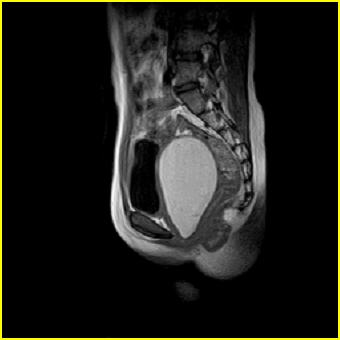

女、15岁、下腹疼痛2天,排尿困难1天。查体:处女膜闭锁,距处女膜约4至5cm处扪及一约5cm直径的圆形包块,张力较高,触痛明显、欠活动。b超提示子宫增大伴宫内增强回声团。

影像意见:子宫直肠陷凹积血。

更正影像意见:阴道积血。

处女膜闭锁,阴道积血

处女膜闭锁,阴道积血,子宫积血.

先天性处女膜闭锁,伴阴道积血,不除外先天性阴道粘液囊肿形成。

阴道积血,子宫积血.

子宫及阴道积血。

处女膜闭锁,伴子宫及阴道积血.